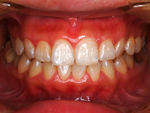

~術前~

歯周治療写真

~術後~